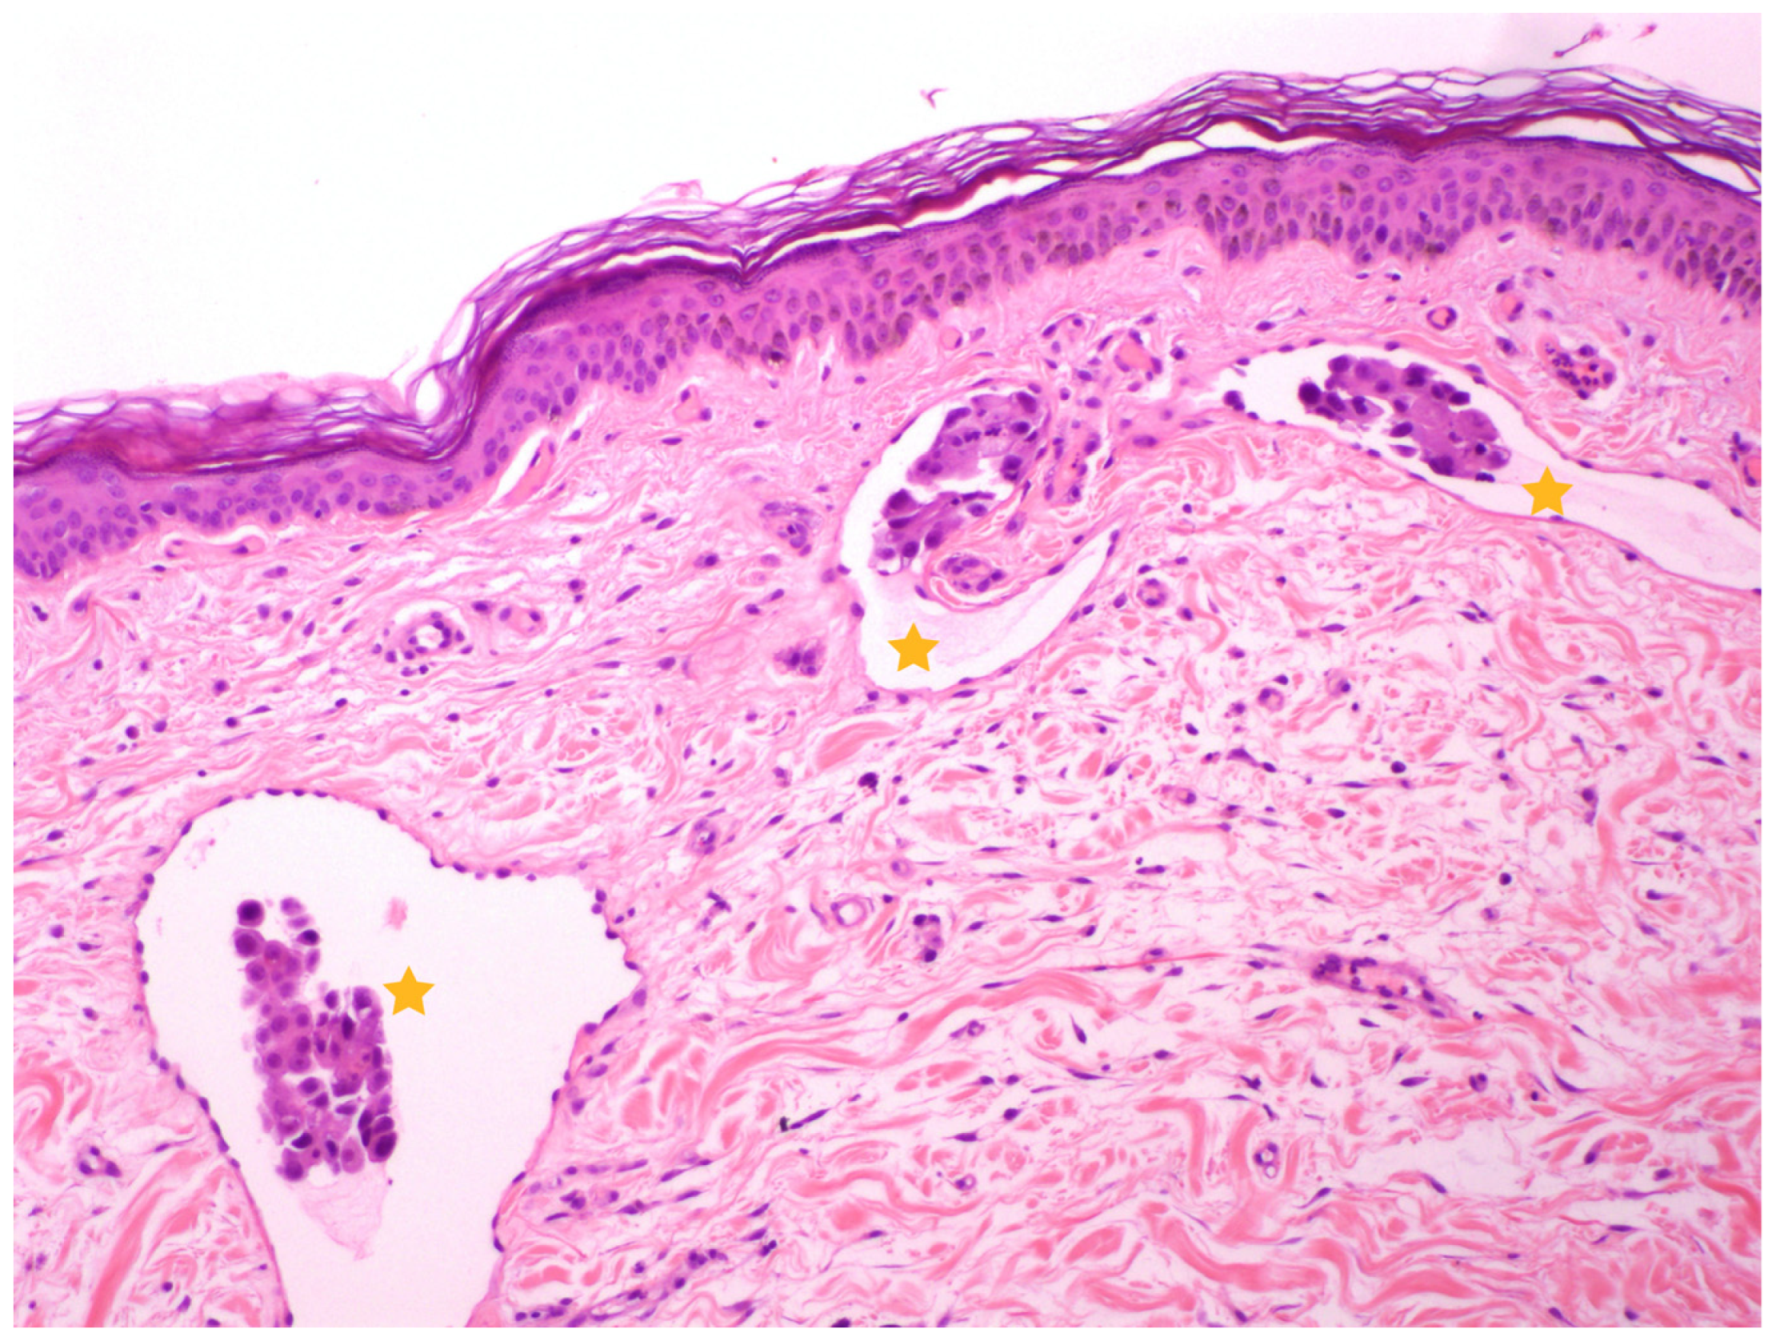

3.1. Dogs and Tumor Characteristics